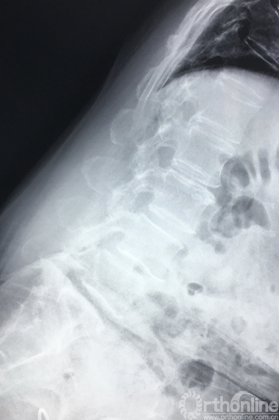

过屈位X片